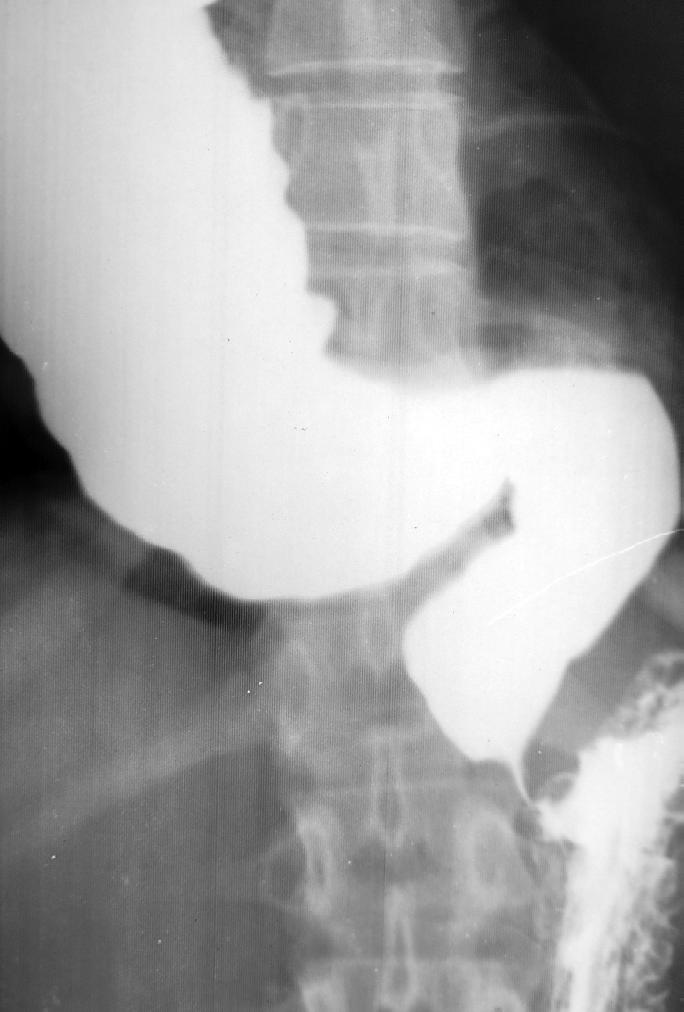

La doi ani postoperator, simptomatologia s-a menținut. Examinarea radiologică a tractului gastrointestinal superior a evidențiat un tranzit intestinal accelerat, cu opacifierea cecului la 8 minute. S-a constatat hiperaciditate gastrică, cu o secreție de acid clorhidric de 142 mEq/l, iar endoscopia digestivă superioară nu a relevat leziuni patologice.

S-a intervenit chirurgical prin vagotomie supraselectivă (VSS) și reconstrucția pilorului.

La doi ani postintervenție, pacienta era asimptomatică, prezentând o creștere ponderală, tranzitul gastrointestinal era normal, cu opacifierea cecului la 4 ore (pasaj baritat). Se remarca o secreție gastrică în limite fiziologice (normoaciditate), endoscopie negativă și manometrie gastrică fără modificări.